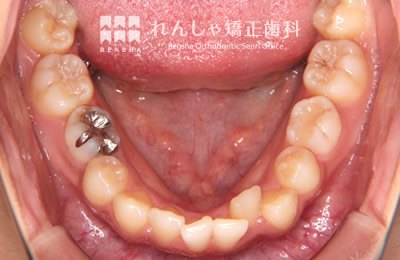

中高生

永久歯列はほぼ完成してしますが、歯列を側方だけでなく後方へも拡大し、埋まっていた右上奥歯を引っ張り出しています。

| 主訴 | 埋まったままでてこない歯がある |

|---|---|

| 診断名 | Angle Class II 小臼歯の埋伏と叢生を伴う上顎前突 |

| 初診時年齢 | 13歳5か月 |

| 装置名 | マルチブラケット装置 |

| 抜歯非抜歯 | 非抜歯 |

| 治療期間 | 2年3か月 |

| 費用の目安 | 約82万円+消費税(検査料金、都度の処置費用等も合わせた総額) |

| リスク副作用 | 歯の移動に伴う軽微な歯根吸収、歯槽骨吸収、歯肉退縮(本症例では軽度の歯根吸収を認めた)、矯正器具装着中のカリエスリスク増大(本症例ではカリエス発生無し) |